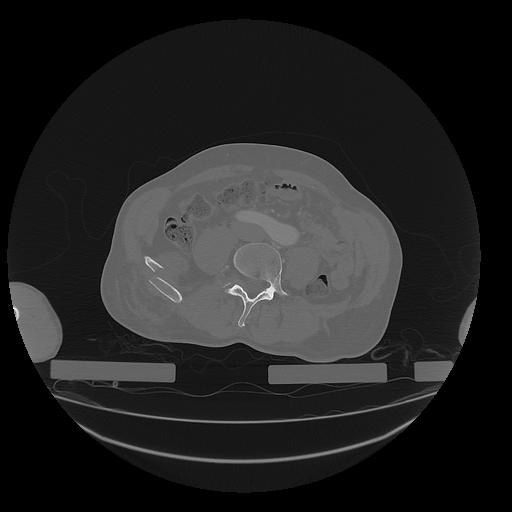

31 PULMON,CE,Vol,1.0,PULMON,,